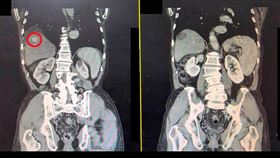

罹肝癌被判剩半年 15公分腫瘤竟變6公分

一位60歲女性,肝臟出現直徑15公分巨大腫瘤,且侵犯...

59歲男罹肝癌 1年後「12公分腫瘤」竟沒了

罹患肝癌不代表走入絕境,胃腸肝膽科醫師錢政弘分享,過...